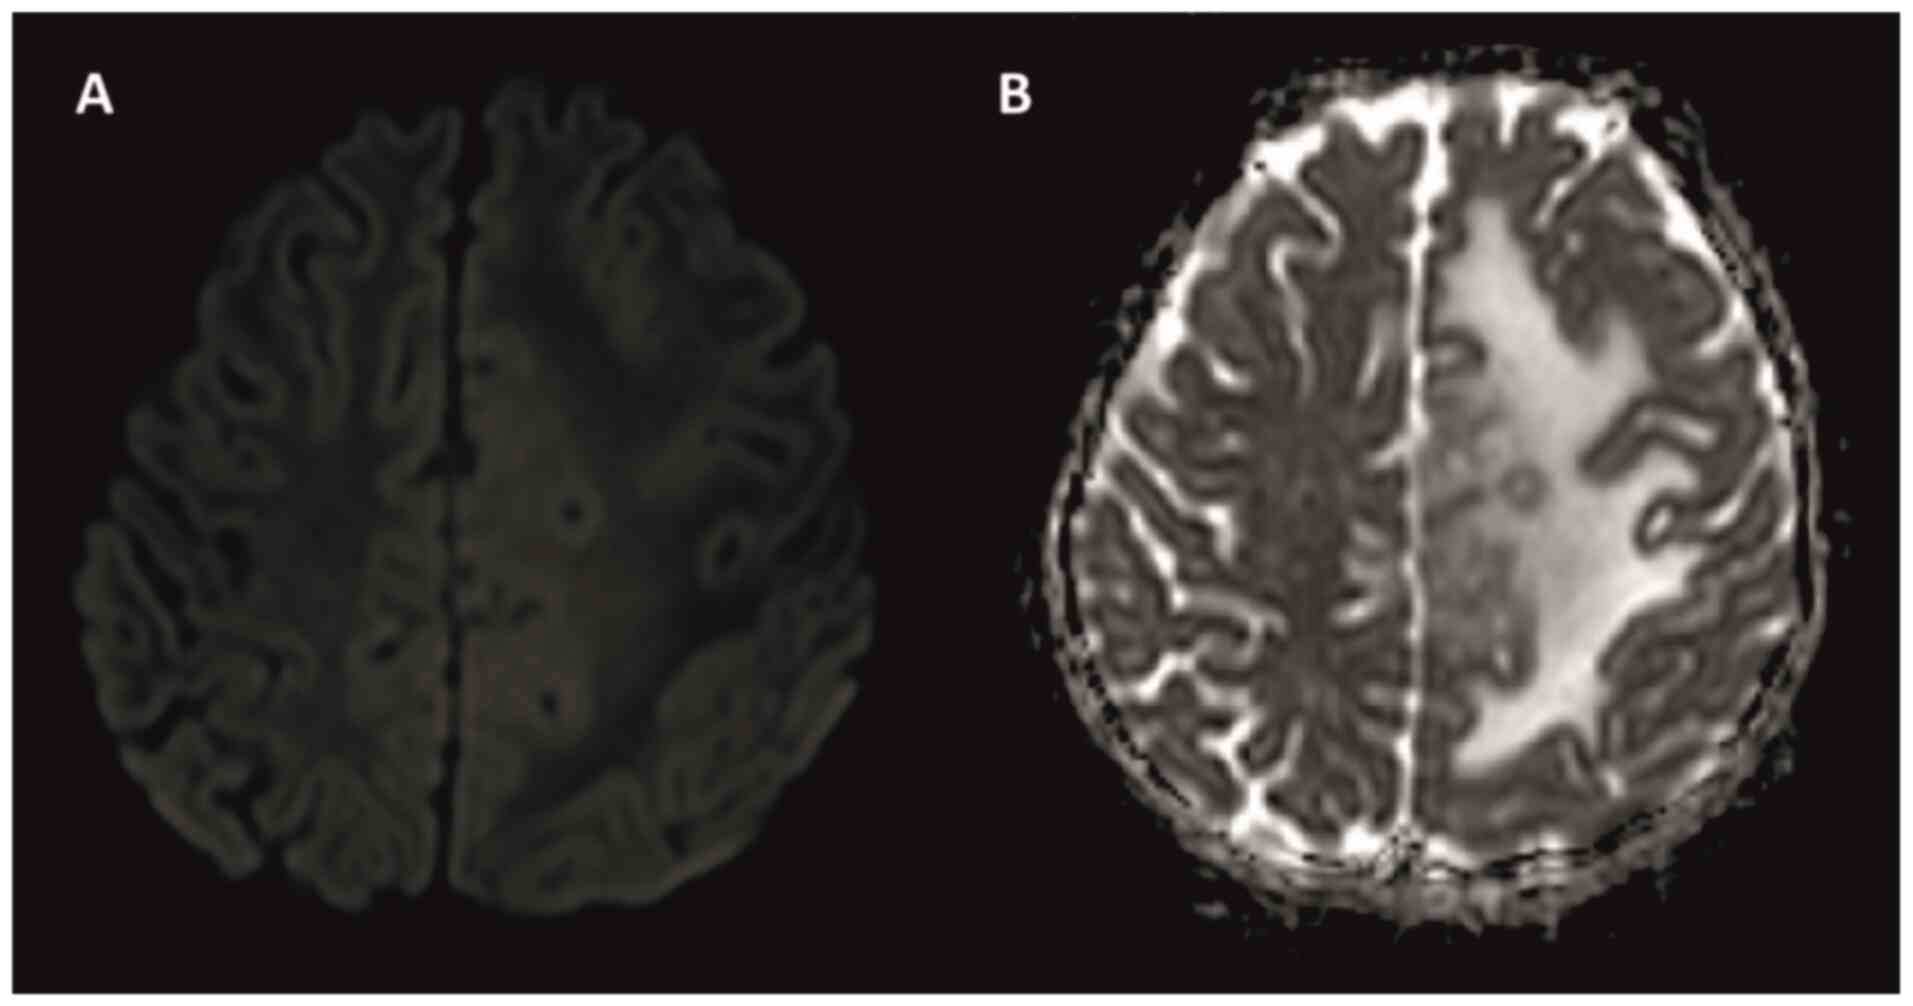

Intracranial tuberculoma represents one of the most severe complications of central nervous system tuberculosis (TB), with an incidence that is relatively low. In cases of intracranial tuberculoma, patients may develop drug toxicity and/or immune reconstitution inflammatory syndrome (IRIS) while receiving anti‑TB treatment. The current study presented the case of a seven‑year‑old female patient with intracranial tuberculoma who developed drug‑induced hepatotoxicity and IRIS during the course of treatment. During the follow‑up of the patient, anti‑TB drug‑induced hepatitis developed, which led to the discontinuation of the drug twice. In the seventh month of treatment, cranial MRI showed the progression of tuberculoma lesions. The possibility of IRIS or treatment failure was considered and the treatment was restarted with steroids and non‑hepatotoxic anti‑TB drugs. With steroid and anti‑TB treatment, the lesions regressed almost completely and the neurological deficit regressed. Patients receiving treatment should be followed up closely due to the possible side effects of anti‑TB drugs, especially IRIS, which develops as an immune restructuring response during the recovery of the immune system.

Figure 1

Figure 2

Figure 3

Figure 4

Figure 5